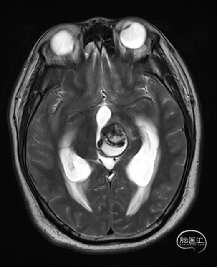

术前MRI检查

术前MRI检查提示左侧丘脑中脑海绵状血管瘤并卒中,梗阻性脑积水;

诊断:1.左侧丘脑中脑海绵状血管瘤并卒中,2.梗阻性脑积水;

年轻患者,较短时间内发生左侧丘脑二次出血,出现右侧面部及上肢麻木,复视,第二次出血后并发梗阻性脑积水,出现头痛。结合病史、神经系统体征、头颅CT及MRI检查,诊断左侧丘脑及中脑CM并卒中、脑积水明确,并导致了神经功能障碍,具备手术指征。

根据MRI及DTI显示,只有在丘脑与上丘之间的点(dot)进入病变才可能在切除病变时最大程度保护神经功能,由于上述原因,该“点”在术中显露极其困难,虽有导航指引,电生理监测的条件下,对术者的耐心、技术、经验及体能依然是极大的挑战;

本例患者磁共振检查清晰显示病变位于左侧丘脑中脑区域,且位于丘脑内下方向中脑顶盖延续,病变的上部、前部、外侧部都有重要的神经组织,因此,手术从上方、前方、外侧方向切除病变均难以实施;